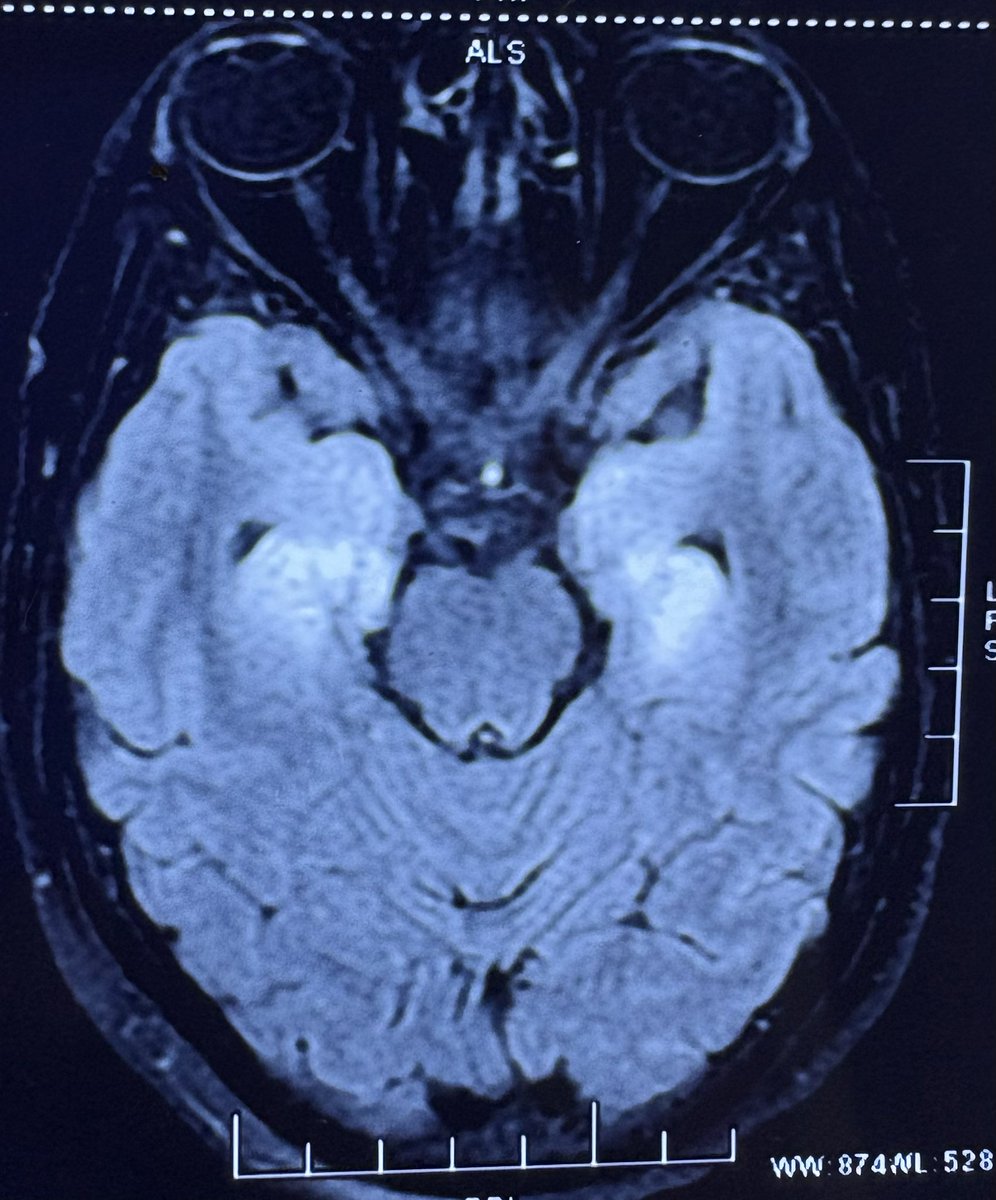

MRV shows left Transverse and sigmoid sinus thrombosis. No improvement after 2 days of IV heparin. Pt requires heavy sedation, ventilation for headache/agitation.